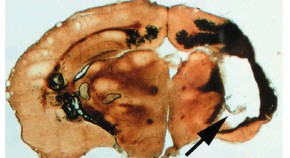

Before stem cell therapies become mainstream, several hurdles must be overcome. One challenge is developing air-tight approaches to assure that stem cell transplantation does not give rise to tumors. Another is finding safe ways to induce pluripotency in adult stem cells, which can then be used for transplantation. In Bedside to Bench, Evan Snyder and Rahul Jandial discuss the risks of tumorigenesis in stem cell therapies, and, in Bench to Bedside, Laura Clarke and Derek van der Kooy examine new ways to induce pluripotency.